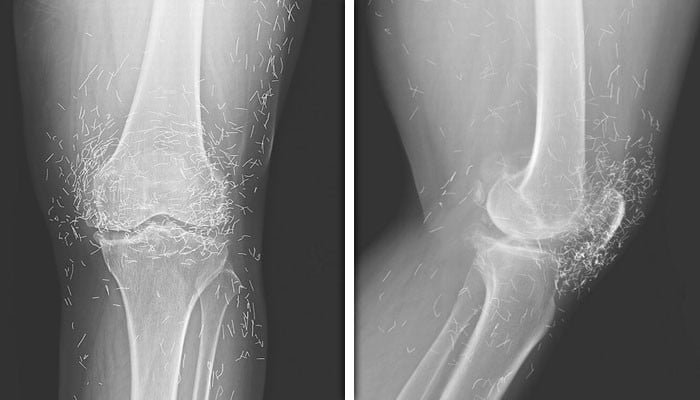

ایکیوپنکچر کروانے سے بھی خاتون کو گھٹنوں کے درد سے نجات نہیں ملی بلکہ درد بڑھنے لگا تو وہ اسپتال گئی تو اس کے بائیں گھٹنے کے ایکس رے سے پتہ چلا کہ جوڑ کے اندرونی حصے میں پنڈلی کی ہڈی موٹی اور سخت ہو گئی ہے۔

ڈاکٹرز کو خاتون کے گھٹنوں کے ایکس رے میں سونے کے چھوٹے چھوٹے سیکڑوں دھاگے بھی نظر آئے جو کہ ایکیوپنکچر کرتے ہوئے گھٹنوں میں ڈالے گئے تھے۔

ڈاکٹروں کو معلوم ہوا کہ یہ دھاگے عورت کے ایکیوپنکچر علاج کے حصے کے طور پر ڈالے گئے تھے۔